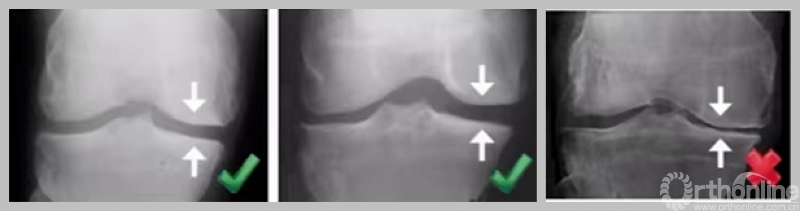

3. 外侧全层软骨完好

负重位及外翻应力位保证外侧间隙正常。

4. MCL功能正常

可复性关节内畸形,屈曲20°,外翻应力位X线片。